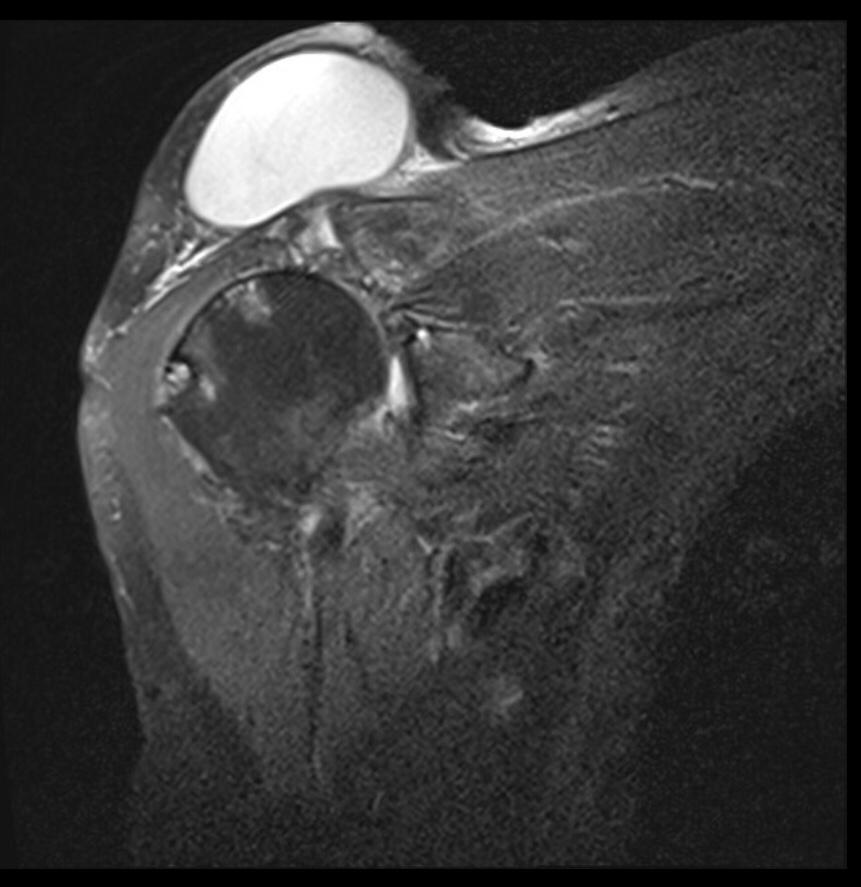

THE GEYSER SIGN IS A SUBCUTANEOUS PSEUDOTUMOR ABOVE THE ACROMIOCLAVICULAR JOINT

The geyser sign is a subcutaneous pseudotumor above the acromioclavicular joint, also known as AC joint cyst. The geyser sign is an infrequently encountered imaging sign that was originally described on conventional fluoroscopy-guided shoulder arthrography. The first case report of these cysts occuring in association with rotator cuff tears was made by Dr. Edward Craig in 1984, and again in 1986. The sign derives its name from its geyser-like appearance.

On physical examination, an AC joint cyst is a palpable fluid-filled mass. MRI scanning or a shoulder arthrogram should be obtained to evaluate the shoulder. Unenhanced MRI scans showing a large rotator cuff tear, a degenerated AC joint, and a large subcutaneous cyst adjacent to the AC joint is virtually patognomonic for the disease. Contrast administration on MR arthrogram will show the synovial fluid or intra-articular contrast extravasates from the glenohumeral joint into the subacromial bursa, into the AC joint, and then into an overlying cystic mass when a full-thickness rotator cuff tear is present, resembling a geyser spouting upwards.

Initial treatment is conservative and involves physical therapy along with aspiration. In patients with functional impairment or chronic shoulder pain who have failed conservative management, surgical treatment is recommended for both excision of the cyst and repair of the rotator cuff tear.